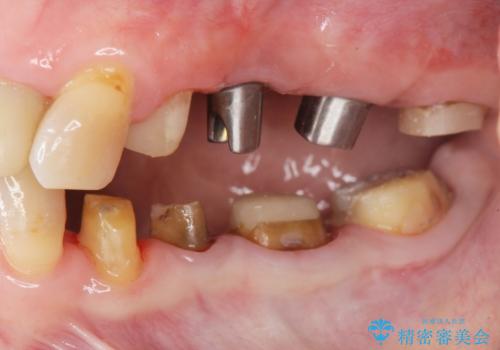

- 見た目の悪い銀歯や虫歯、歯の欠損、全体的な治療を希望されて来院されました。

インプラント治療や根管治療・セラミック治療を総合的に考えた精度の高い治療を計画し、しっかり噛めるようになるのはもちろん長期的な予後や審美性の向上を考えた全顎的な治療を実践していきます。